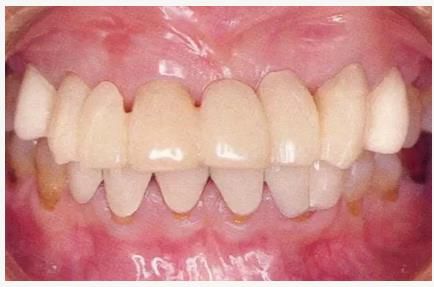

圖6-9 牙周外科治療5個月后,最終取模前的狀態(tài)?;乐車@得了充足的附著齦。

圖6-10 佩戴最終修復(fù)體時的X光照片。